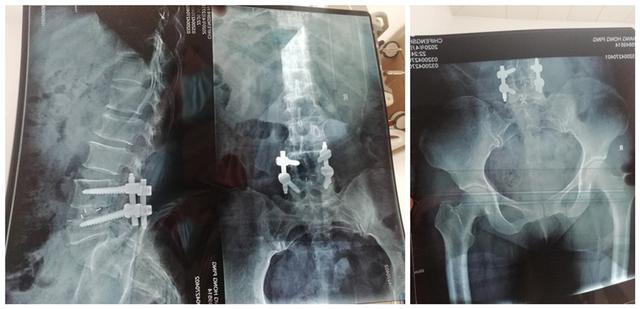

小姨子的阿姨今年42岁,以前因为椎间盘突出做过固定融合手术,今天突然被车撞了,现在躺在床上翻身都困难。片子也拍了,没有问题!本来没有问题是一件开心的事情,但是小姨子的心里却很不平衡,她阿姨疼成这个样子,最后没有问题,这可怎么办呢?于是就找到了我。我让她把片子发给我看看:

结果她拍了照片过来,但片子照的技术不行,本来想好好教育教育小姨子的,但一想万一小姨子去我老婆那告状我就惨了,所以将就看吧。这两张片子分别是腰部和髋部的片子,医生考虑的是非常全面了,确实没发现有骨折,以前手术部位的钉子和融合器也没有问题。